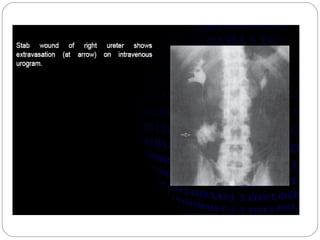

Extravasation of contrast medium

Local pain, erythema, swelling

Usually resolve with local therapy

Rarely, significant tissue necrosis and skin-

sloughing occur (even with small amounts)